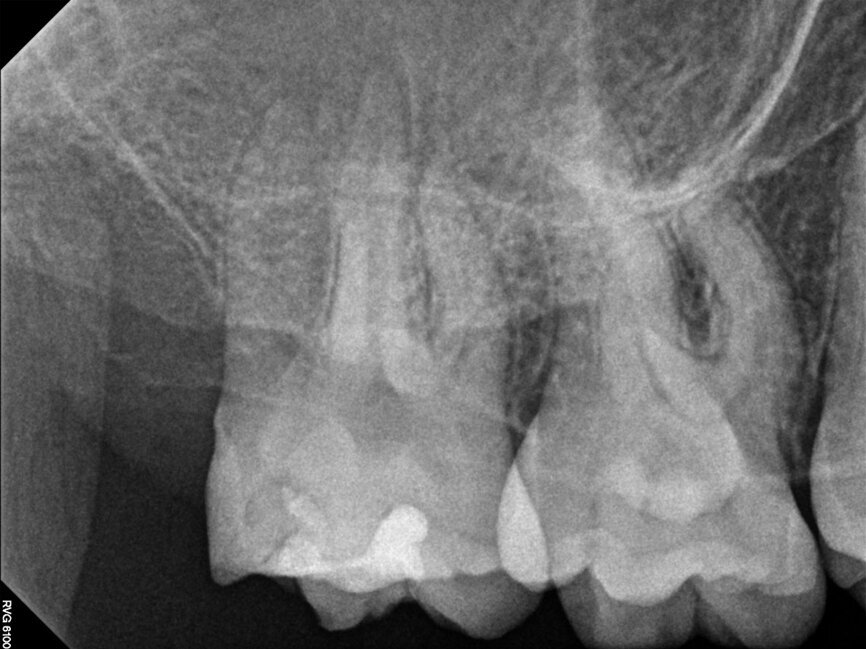

Fig. 15a: Cased treated with PIPs (Photon Induced Photoacoustic Streaming). Note the orifice barrier placed in composite to protect the endodontic treatment from coronal leakage. (Courtesy of Dr. Paula Elmi)

Fig. 15b: Cased treated with PIPs (Photon Induced Photoacoustic Streaming). Note the orifice barrier placed in composite to protect the endodontic treatment from coronal leakage. (Courtesy of Dr. Paula Elmi)

Fig. 15c: Cased treated with PIPs (Photon Induced Photoacoustic Streaming). Note the orifice barrier placed in composite to protect the endodontic treatment from coronal leakage. (Courtesy of Dr. Paula Elmi)

Fig. 15d: Cased treated with PIPs (Photon Induced Photoacoustic Streaming). Note the orifice barrier placed in composite to protect the endodontic treatment from coronal leakage. (Courtesy of Dr. Paula Elmi)

Fig. 15e: Cased treated with PIPs (Photon Induced Photoacoustic Streaming). Note the orifice barrier placed in composite to protect the endodontic treatment from coronal leakage. (Courtesy of Dr. Paula Elmi)

Fig. 15f: Cased treated with PIPs (Photon Induced Photoacoustic Streaming). Note the orifice barrier placed in composite to protect the endodontic treatment from coronal leakage. (Courtesy of Dr. Paula Elmi)

Fig. 15g: Cased treated with PIPs (photon-induced photoacoustic streaming). Note the orifice barrier placed in composite to protect the endodontic treatment from coronal leakage (courtesy of Dr. Paula Elmi).